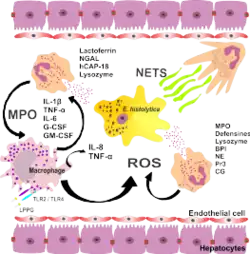

Due to the difficulty of exploring host and amebic factors involved in the pathogenesis of amebic liver abscess in humans, most studies have been conducted with animal models (e.g., mice, gerbils, and hamsters). Histopathological findings revealed that the chronic phase of amebic liver abscess in humans corresponds to lytic or liquefactive necrosis, whereas in rodent models there is granulomatous inflammation. However, the use of animal models has provided important information on molecules and mechanisms of the host/parasite interaction in amebic liver abscess.[4]

- ^ a b Campos-Rodríguez, Rafael; Gutiérrez-Meza, Manuel; Jarillo-Luna, Rosa Adriana; Drago-Serrano, María Elisa; Abarca-Rojano, Edgar; Ventura-Juárez, Javier; Cárdenas-Jaramillo, Luz María; Pacheco-Yepez, Judith (2016). "A review of the proposed role of neutrophils in rodent amebic liver abscess models". Parasite. 23: 6. doi:10.1051/parasite/2016006. PMC 4754534. PMID 26880421.